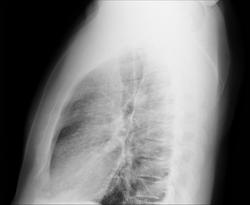

Мужчина, 30 лет. Жалоб нет. Обследование с проф.целью. Боковой срезан (такой снимок принес).

Диффузное усиление легочного рисунка, я бы такого подробно попытала по анамнезу + архив, если есть

В 70 лет такие лёгкие были бы приемлимы, а для 30 -  не красавец. Можно думать о легочной форме саркаидоза. В анамнезе покопаться, может, профвредность какая-нибудь имеется.

Проф патологию надо исключать . Корни легких выглядят довольно спокойными , сохраняя структурность.

Корни, да и легочный рисунок, на мой взгляд, вполне соответствуют комплекции пациента. Жалоб нет - здоров. Утолщение междолевой плевры. В левой верхушке,может, кальцинат. Если же хочется с чем-то разобраться, то это процесс длительный, с учетом всех амнестических, клинических данных, с приминением диагностических алгоритмов лучевой диагностики, в том числе - скопии, томографии.

Скорее профпатология. Уточняйте анамнез. Архив.